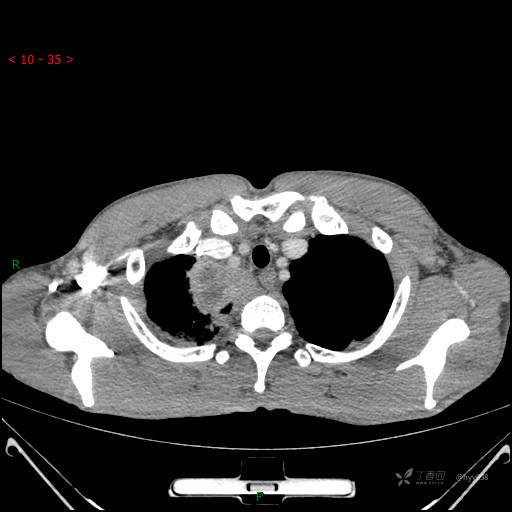

胸部CT平扫